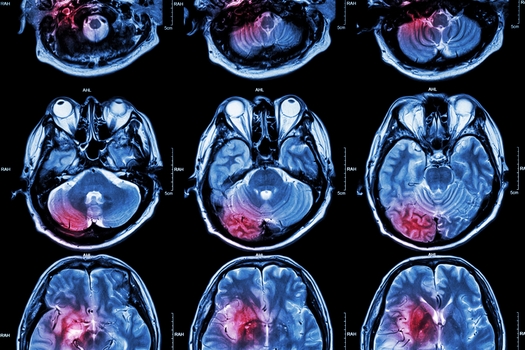

During February, Americans are urged to pay closer attention to their heart health. Experts say new findings suggest it can keep your brain in better shape.

Researchers in Arizona and elsewhere are searching for ways to prevent heart attacks and strokes, which could slow the onset of dementia.

With American Heart Month under way, the American Heart Association's statistics update says in the past decade, global rates from Alzheimer's and other forms of dementia have grown at a faster pace than heart-disease rates.

"That boundary that we used to draw," said Elkind, "between vascular diseases of the brain, like stroke, and degenerative problems, like Alzheimer's disease, is beginning to fade away."

The report says efforts such as keeping blood pressure low can reduce the risk of dementia later in life. The study also found gender, racial and ethnic disparities that are prevalent among people with poor brains health

"We are seeing an increase in cardiovascular disease and strokes," said Elkind, "and that might lead to an increase down the line in people with not just dementia, but all sorts of long-term, chronic health issues."

Researchers at the University of Arizona are working on a promising treatment to reduce the risk of dementia in patients who have had a stroke.

Kristian Doyle, associate professor of immunobiology, University of Arizona College of Medicine - Tucson, said they are investigating a drug that helps the brain safely store cholesterol after a stroke without provoking an inflammatory response.

"What's good for vascular health is good for both organs," said Doyle. "That's the main point to get across, really, is how healthy your blood vessels are. And unhealthy vessels are the cause of strokes and heart attacks. And stroke is a risk factor for the development of Alzheimer's."

Doyle said up to one-third of the people who have a stroke will develop dementia in the months afterward, adding that strokes affect more than 15 million people in the world every year.